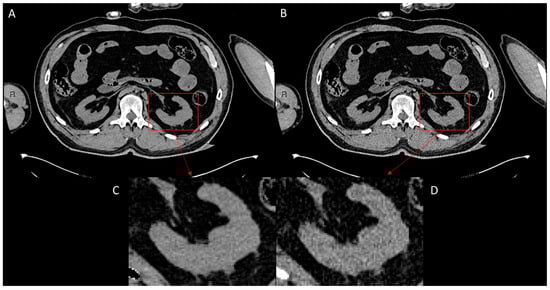

To evaluate the performance of ErisNet on the test set, we implemented a comprehensive protocol [] to assess the model’s efficacy in noise reduction and its subsequent impact on CT image quality. The following results indicate ErisNet’s performance across various metrics, demonstrating a significant reduction in noise compared with the original LQ images (Figure 4).

Figure 4.

Comparison of CT image quality before and after processing with ErisNet, with detailed enlargements. (A) Image processed with ErisNet, showing significantly reduced noise levels and increased sharpness. (B) Corresponding low-dose image, used as input for ErisNet, showing increased noise. (C) Magnified view of a specific region of interest (red box), the left kidney, in image (A), highlighting the noise reduction and detail preservation achieved by ErisNet. (D) Magnified view of the same region of interest (red box) of the left kidney in image (B), illustrating the significant noise present in the original low-dose image before processing.